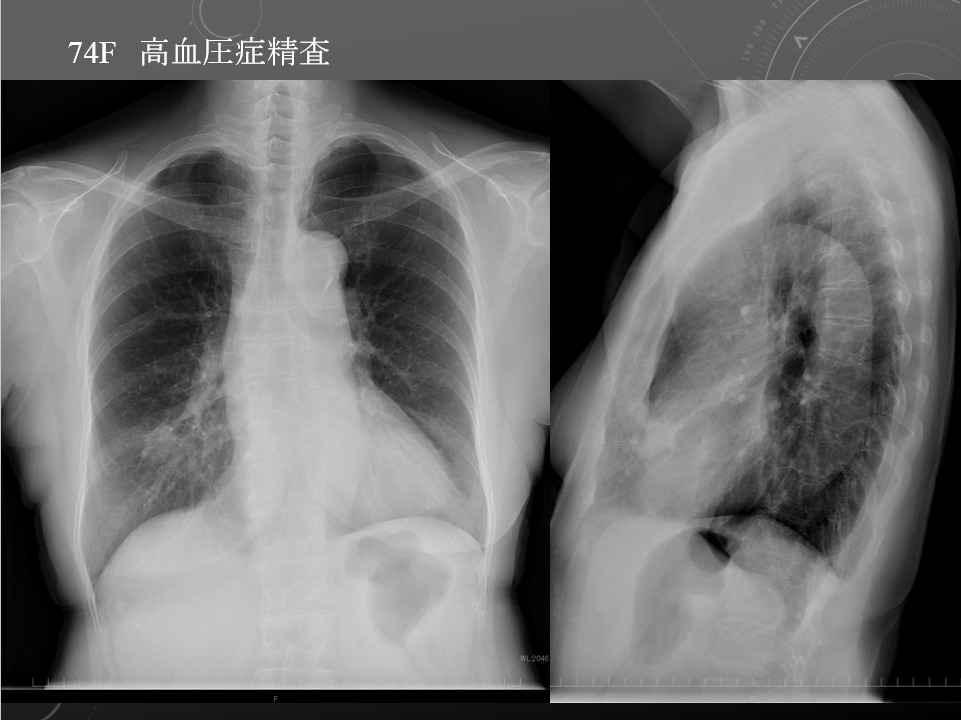

74F 高血圧スクリーニング 右肺中葉原発性肺腺癌